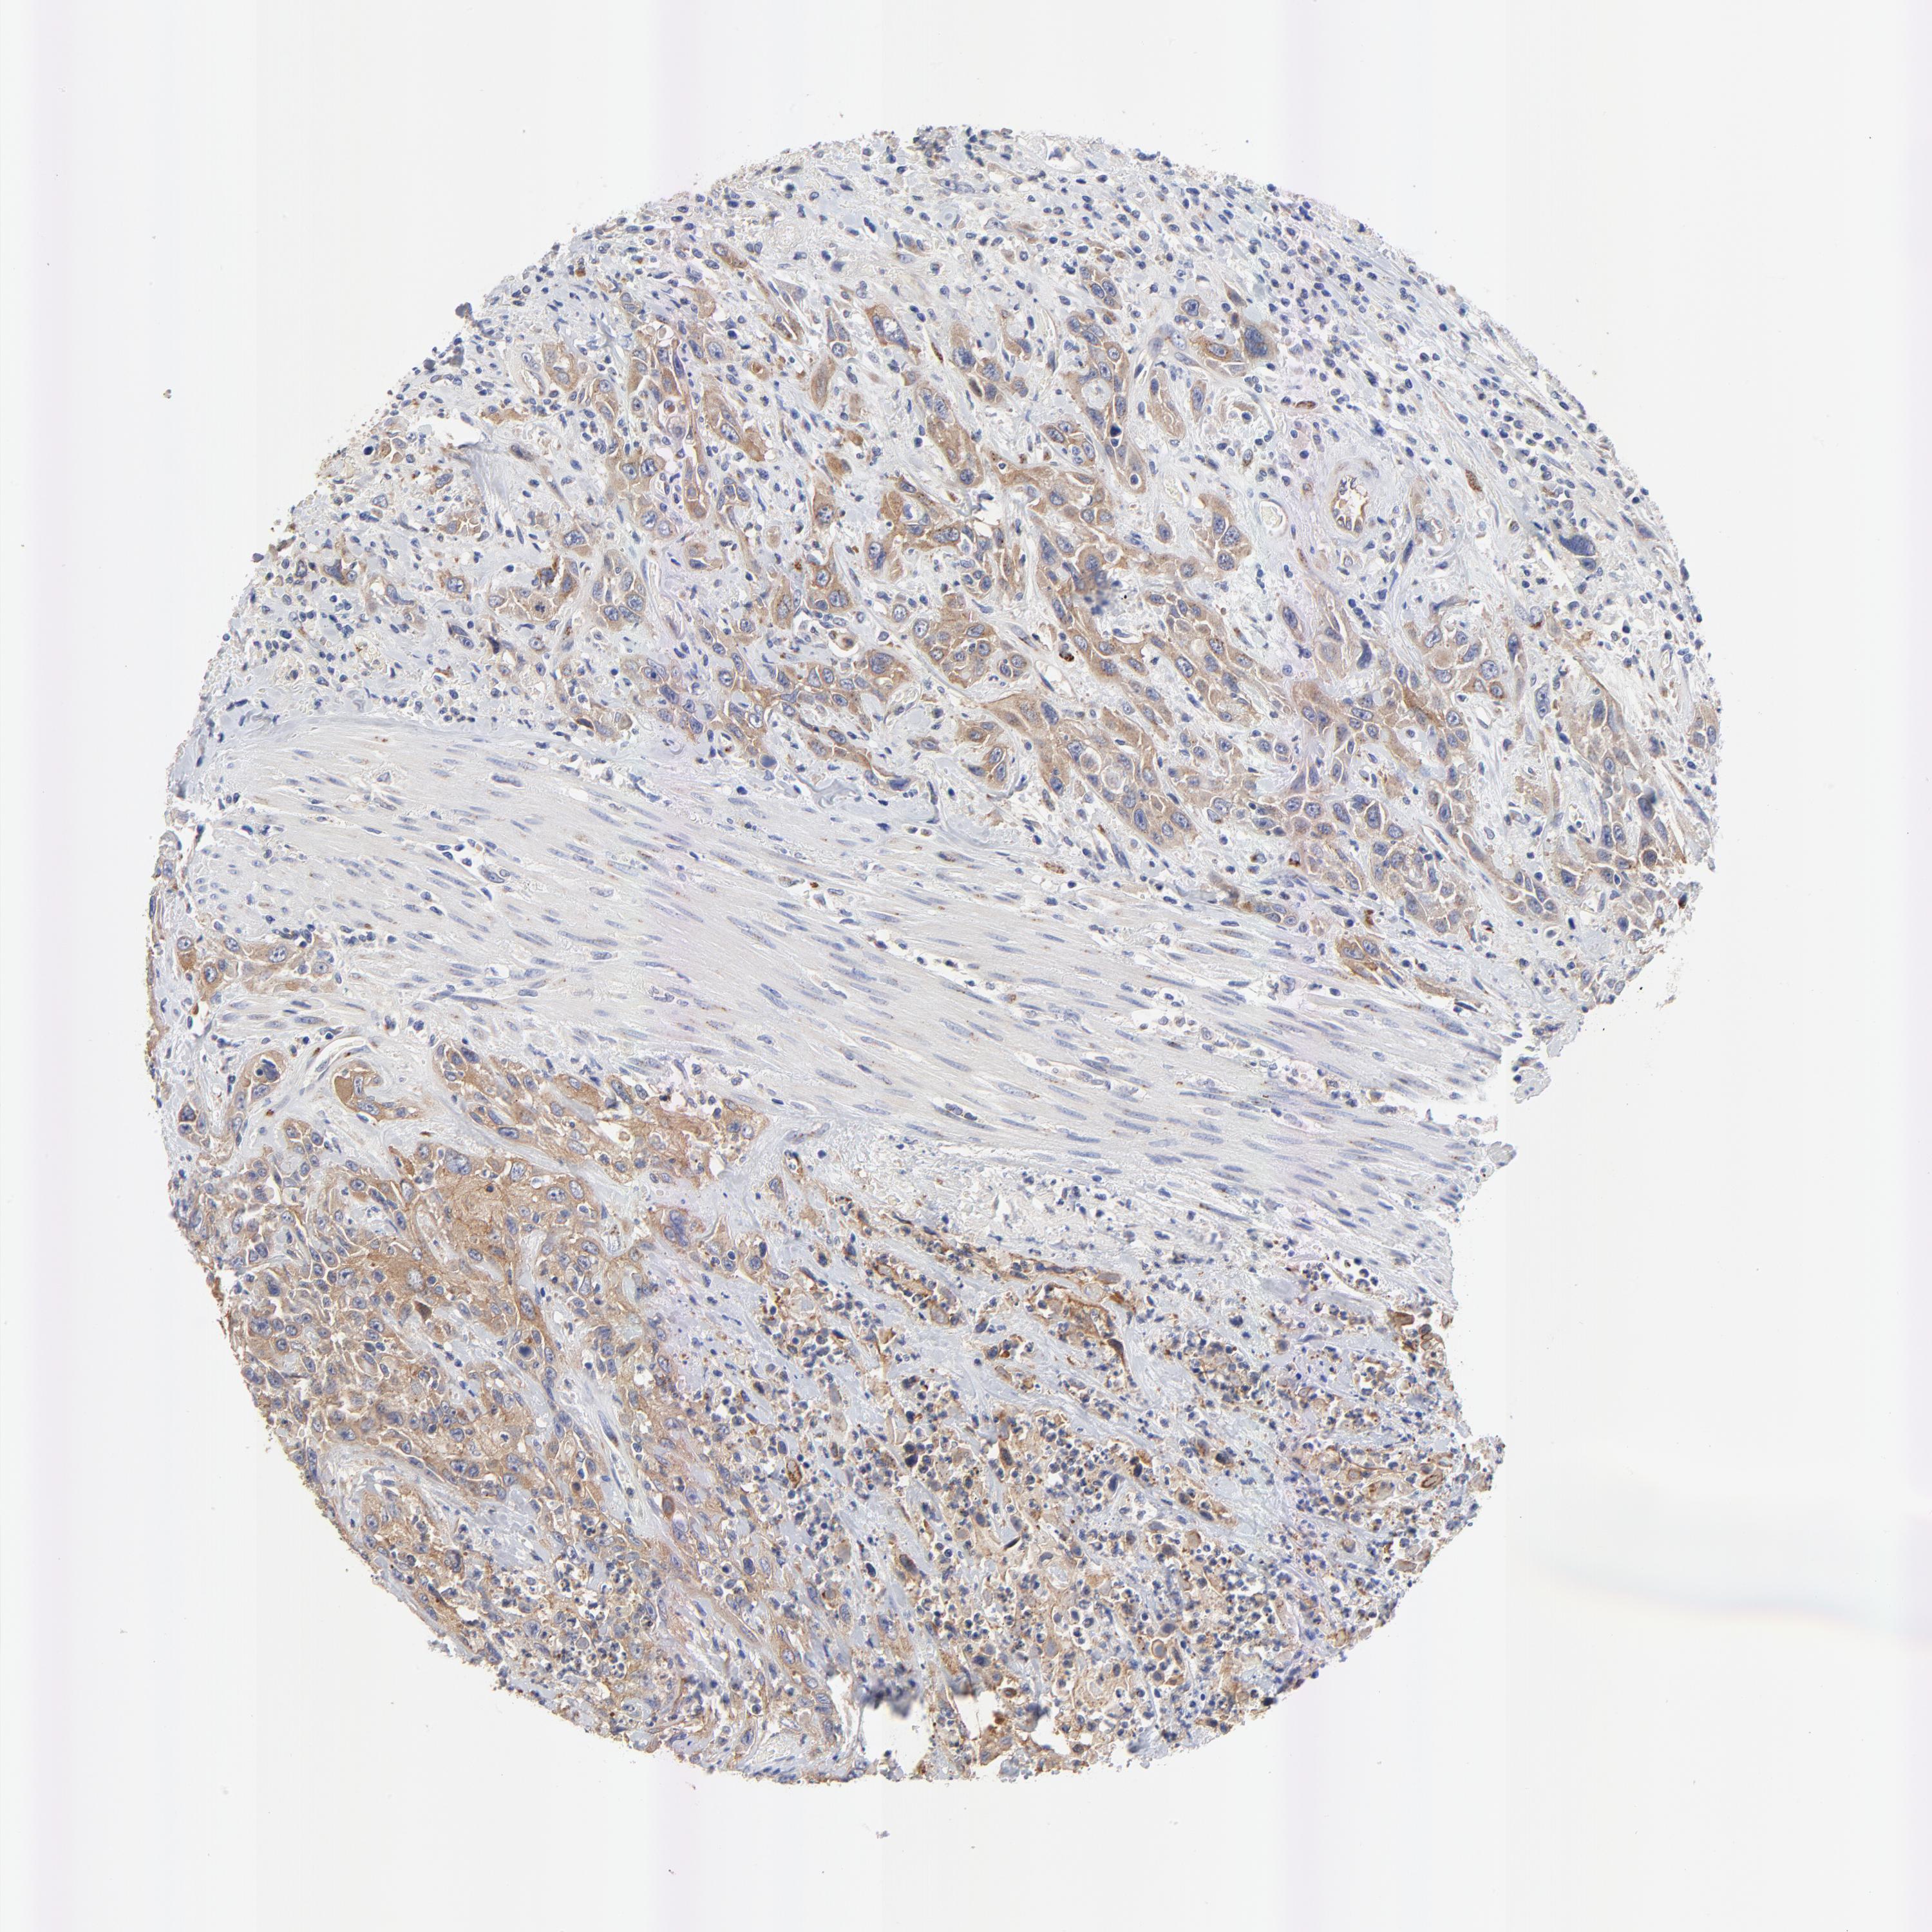

UROTHELIAL CANCER - Protein expressioni

A mouse-over function shows sample information and annotation data. Click on an image to view it in a full screen mode. Samples can be filtered based on level of antibody staining by selecting one or several of the following categories: high, medium, low and not detected. The assay and annotation is described here.

Note that samples used for immunohistochemistry by the Human Protein Atlas do not correspond to samples in the TCGA dataset.

Antibody stainingi

Antibody staining in the annotated cell types in the current human tissue is reported as not detected, low, medium, or high, based on conventional immunohistochemistry profiling in selected tissues. This score is based on the combination of the staining intensity and fraction of stained cells.

Each image is clickable and will lead to virtual microscopy that enables deeper exploration of all samples and also displays staining intensity scores, fraction scores and subcellular localization as well as patient and tissue information for each sample.

Antibody HPA003240

Staining

High

Medium

Low

Not detected

Intensity

Strong

Moderate

Weak

Negative

Quantity

>75%

75%-25%

<25%

None

Location

Nuclear

Cytoplasmic/membranous

Cytoplasmic/membranous,nuclear

Urothelial carcinoma, High grade

Urothelial carcinoma, Low grade